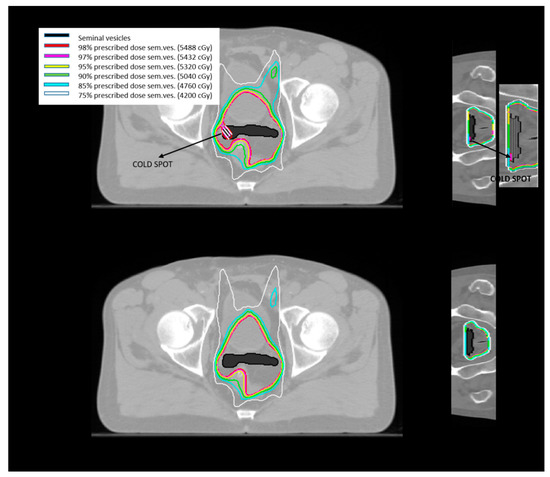

- Tomé, W.A.; Fowler, J.F. On cold spots in tumor subvolumes. Med. Phys. 2002, 29, 1590–1598. [Google Scholar] [CrossRef]